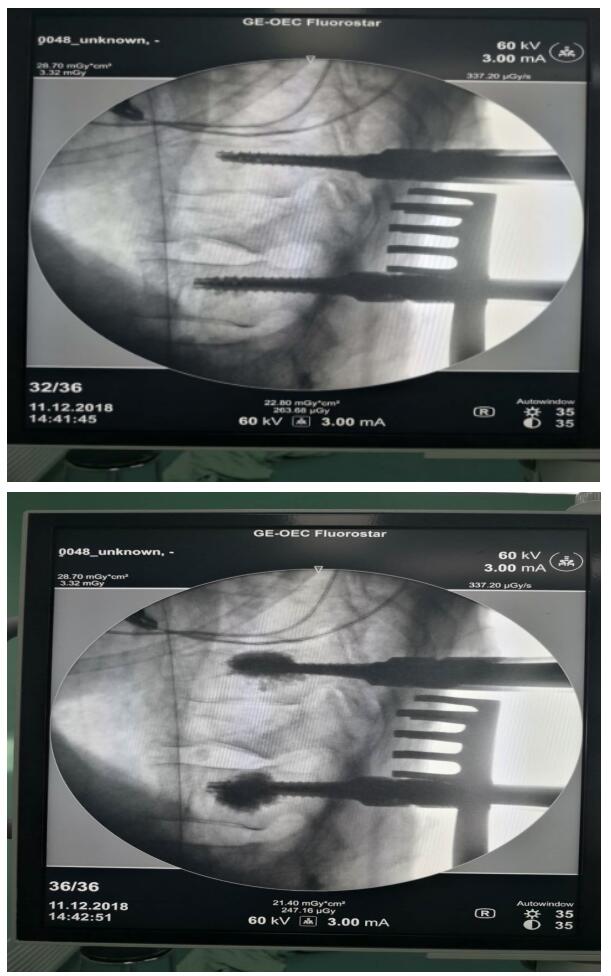

刘涛主任医师和其他医生在综合各种因素后,决定为患者实施“椎板减压骨水泥钉椎弓根系统内固定术”。术后患者的症状明显改善,双下肢肌力善为4级。此例骨水泥钉术为乌海市首例,手术的成功也填补了乌海市在此技术领域的空白。此项手术技术的开展,对于老年人、骨质疏松等患者具有显著意义,缩短了术后恢复时间,减轻了家庭负担。